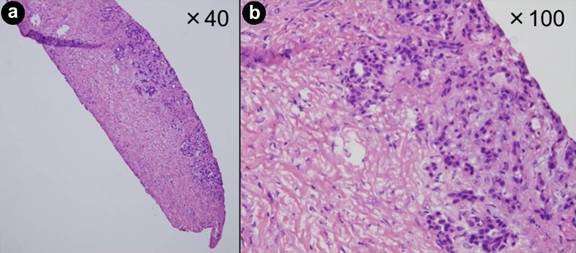

LUS-guided CNB was performed using an 18-gauge needle that was introduced through the right anterior abdominal wall above the pancreatic tumor (Figure 1). Tumors with cystic components were excluded to avoid the risk of peritoneal dissemination resulting from needle puncture. Before the CNB, we dissected a part of the omentum and opened the omental bursa using two laparoscopic dissectors through 5-mm working ports to observe the distal pancreas and directly puncture the tumors. All punctures were performed several times under LUS from a laparoscopic view. Ultrasonographic procedures consisted of the following three steps: (1) measurement of tumor location and size, (2) a search for critical vessels around the tumor using Doppler mode, and (3) a confirmation of safe puncture sites in the tumor (Figure 2). If critical vessels crossed the puncture line, we aborted the biopsy and later switched to EUS-FNA. The obtained tissue samples were used for frozen sections and the final pathological diagnosis (Figure 3). Immediate LUS-guided CNB-related complications were recorded during the procedure, and patients were monitored for late complications (>24 h postoperatively) before discharge. Umbilical open wounds were sutured with absorbable sutures.

Figure 3. Pathological images of a core needle biopsy (CNB) sample of pancreatic adenocarcinoma with hematoxylin-eosin staining. a. A stick of tissue was collected using a Tru-Cut needle. b. Not only the cancer nest, but also the neighboring connective tissue was gathered without destruction of the tissue structure. |

A large-scale analysis of gene expression has been widely proposed as a powerful method for the diagnosis and identification of predictive factors for the treatment of various malignant tumors [28-31]. The availability of tumor tissue is critical for an accurate assessment of gene expression, and laser microdissection and primary cell cultures may be useful tools to separate tumor cells from stromal reactions [6]. Ashida et al. reported an analysis of mRNA related to gemcitabine sensitivity using a high-fidelity RNA amplification technique that allowed analysis of gene expression profiles from EUS-FNA samples of unresectable pancreatic cancer [28]. However, contamination of normal tissue with tumor tissue obtained by the EUS-FNA procedure may be a major obstacle to an accurate analysis. If we need to know only confirmation of the tumor malignancy, EUS-FNA may be enough for the diagnosis. But the sufficiently large amount of tissue obtained by CNB may help allow determination of differences in the genetic characteristics of tumor and normal tissue using advanced tissue extraction techniques such as laser microdissection. The tissue samples obtained from an 18-gauge needle had not only cancer tissue, but also environmental connective tissue in this series. Although multidisciplinary approaches such as chemotherapy and chemoradiotherapy are applicable for treatment of locally advanced unresectable pancreatic cancer, it is still controversial that which is better for the initial therapy [32, 33]. This technique may contribute to genetic analyses that will help determine the best treatment options, such as the selection of an antitumor reagent, and evaluations of the radiosensitivity of pancreatic cancer in the future. It is also important that we need to set the criterion for selection of the patients who receive the profit of this technique in control of cancer.